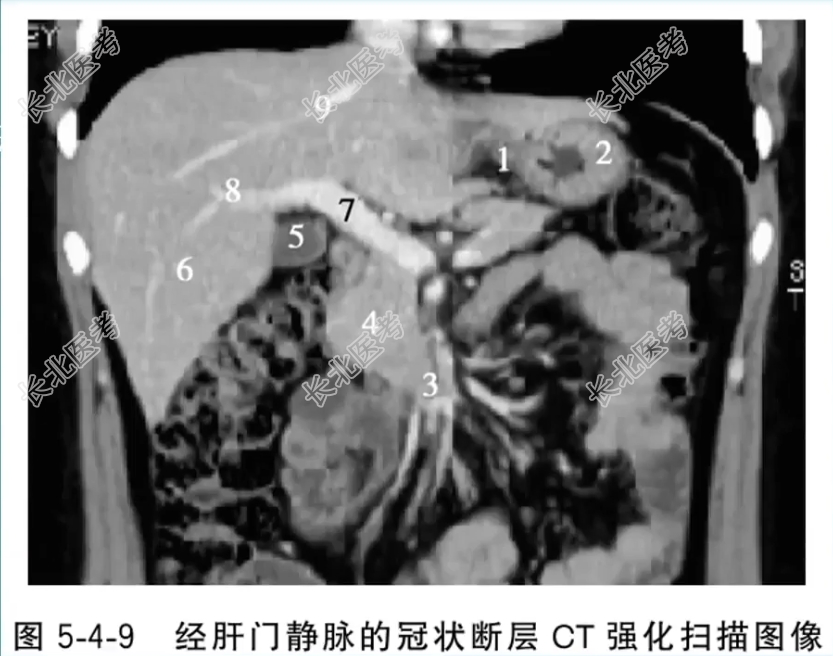

- 单项选择题经肝门静脉的冠状断层CT强化扫描图像中,标记为5的结构是

A、网膜囊

B、胃底

C、胆囊

D、肝右前叶

E、门静脉主干